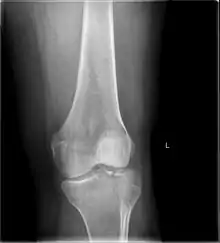

Lateral Tibial Plateau fracture XRay with Depression